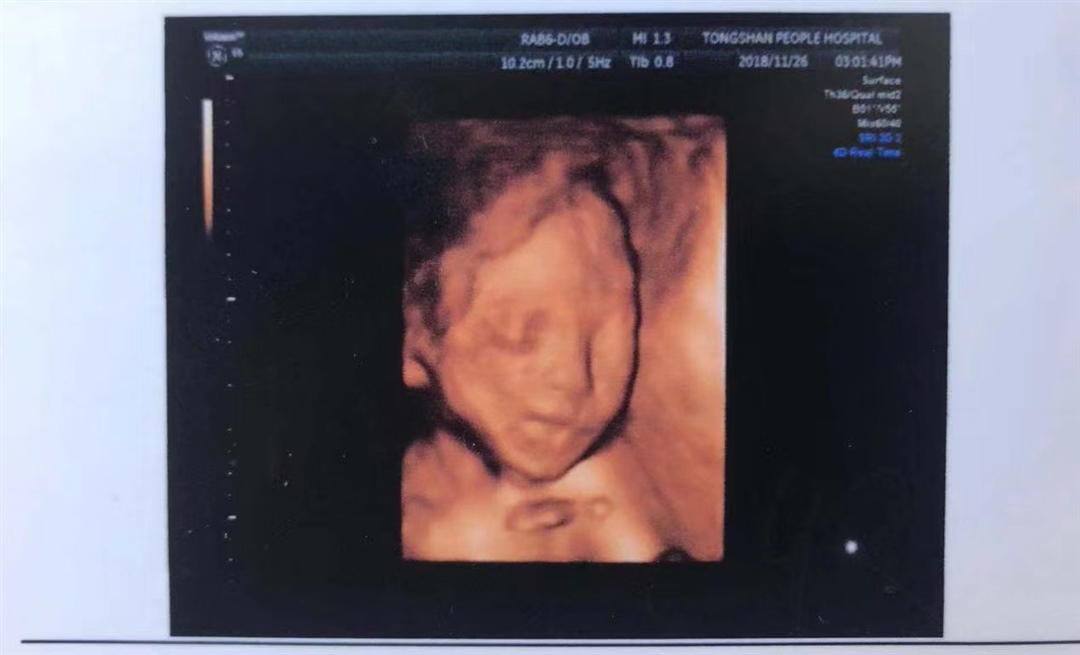

孕35周+0天

很像很像 只不过现在脸上肉嘟嘟啦